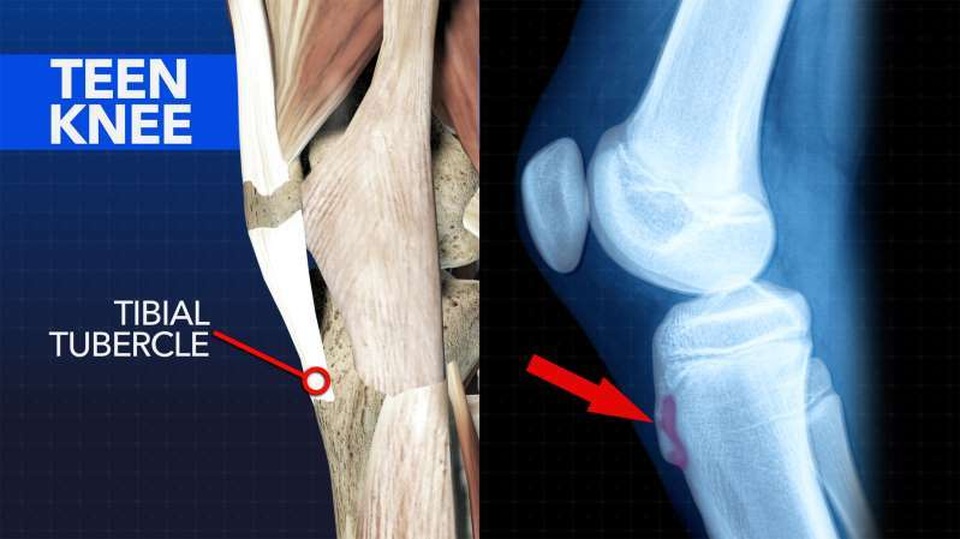

Mọi người hay nghĩ đến đau khớp gối ở người lớn nhưng thanh thiếu niên cũng rất hay bị đau khớp gối, đặc biệt là trong giai đoạn “lớn nhanh”. Điều này làm giảm sự linh hoạt của cơ bắp và cảm giác căng hoặc đau ở sụn tăng trưởng ở đầu gối được gọi là Osgood-Schlatter. Các vấn đề về khớp gối hay gặp nhất ở các vận động viên thiếu niên trong giai đoạn tăng trưởng (đối với nữ, từ 10 đến 14 tuổi; đối với nam, từ 12 đến 14 tuổi).

Cách khắc phục: Những cách khắc phục khớp gối Osgood-Schlatter bao gồm dùng con lăn bọt biển để thư giãn cơ quanh cẳng chân và sử dụng băng nẹp khớp gối để giảm áp lực đè lên lồi củ xương chày, vùng khớp cấu tạo bằng sụn và dễ bị thương khi chạy nhảy.